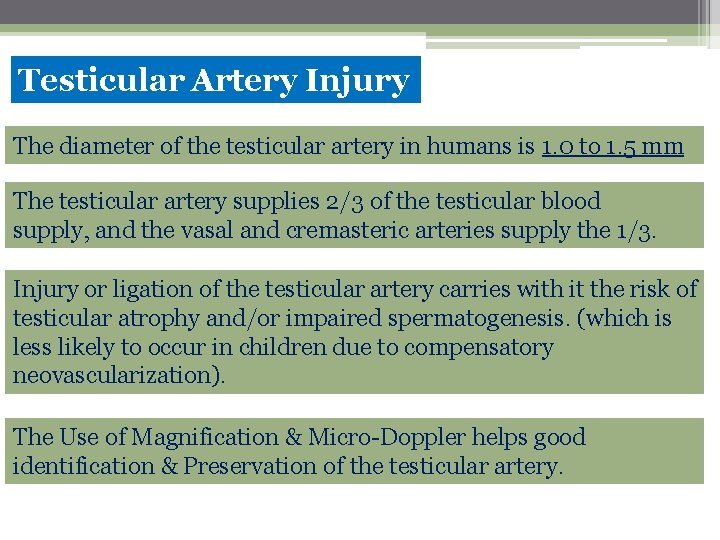

Testicular Artery Injury The diameter of the testicular artery in humans is 1. 0 to 1. 5 mm The testicular artery supplies 2/3 of the testicular blood supply, and the vasal and cremasteric arteries supply the 1/3. Injury or ligation of the testicular artery carries with it the risk of testicular atrophy and/or impaired spermatogenesis. (which is less likely to occur in children due to compensatory neovascularization). The Use of Magnification & Micro-Doppler helps good identification & Preservation of the testicular artery.